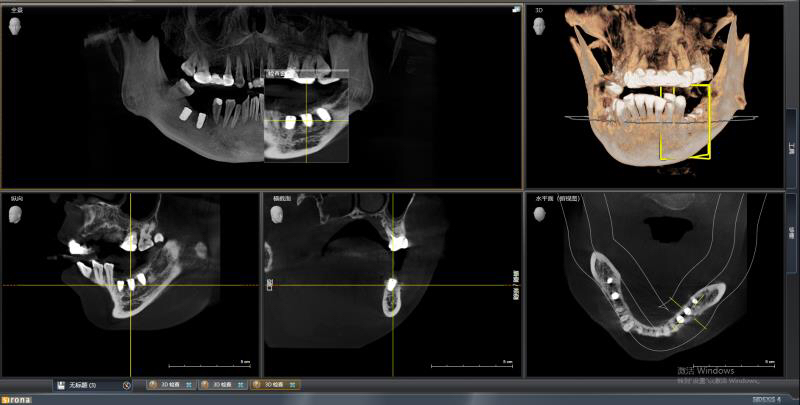

患者中年女性,左下5、6、7缺失多年,牙槽骨吸收较多,CBCT可见牙槽骨高度不足,距离下颌神经管比较近,所以为这位患者选择了短植体进行种植,术中植骨盖膜,历时7个月戴上了牙齿,患者使用满意。